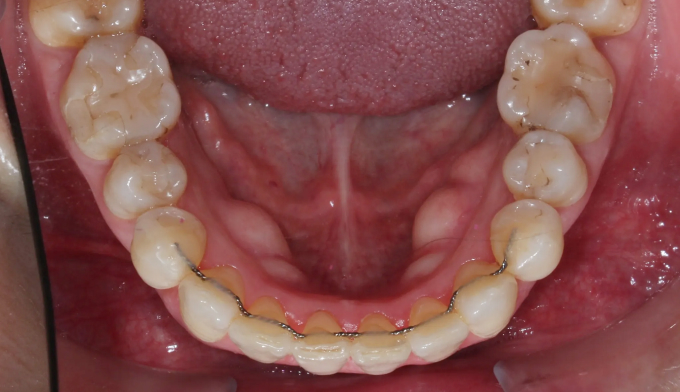

덧니

교정치료에 나이 제한은 없습니다.

건강한 잇몸을 가지고 있다면 60,70대에도 전혀 문제없고, 잇몸이 건강하지 못하다면 20대여도 교정이 힘들 수 있습니다.

아무래도 나이가 있으면 세포활성이 떨어지고 피부의 탄력도 줄어들기 마련입니다.

따라서 섣불리 발치교정을 진행하여서는 안됩니다. 오히려 교정후에 더 나이들어 보이는 경우가 생길 수 있기 때문입니다.

비발치교정을 통하여 치아를 배열하고 일부러 앞니를 조금 더 앞으로 이동시켜 깊어진 팔자주름을 옅게 만들어주었습니다.